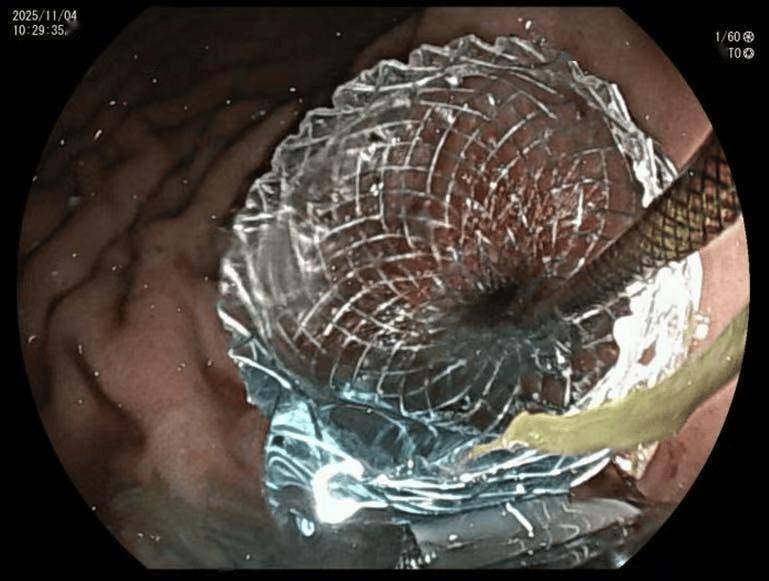

肚子上鼓包消失,肚子也不胀了,时隔一年终于能拔掉鼻饲管自己吃饭,感觉浑身都有劲了!没想到消化科的专家们用这么神奇的办法解决了我吃饭的问题! 11月10日,郎先生出院前满怀激动地对北医三院消化科团队表示